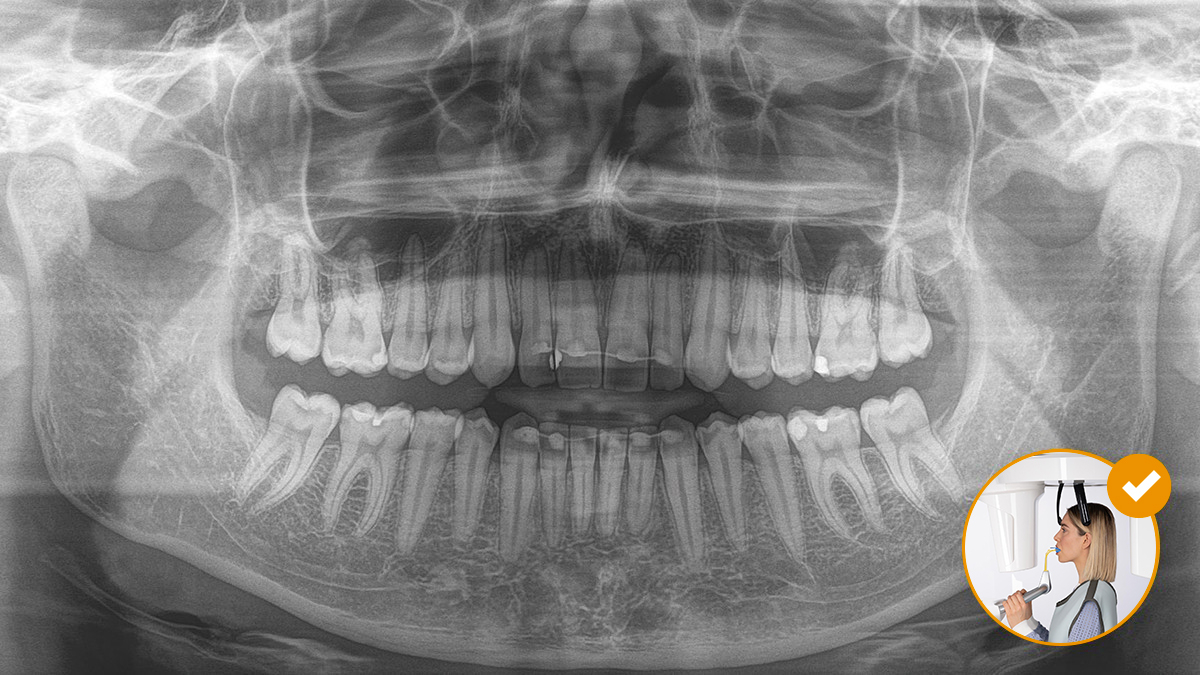

Le positionnement correct du patient permet d’obtenir une qualité d’image élevée pour un diagnostic précis et améliore l’expérience du patient.

Voici notre concept de positionnement du patient et d’imagerie radiographique en 10 points. Deux éléments essentiels : une qualité d’image élevée et le confort du patient et de l’assistant.